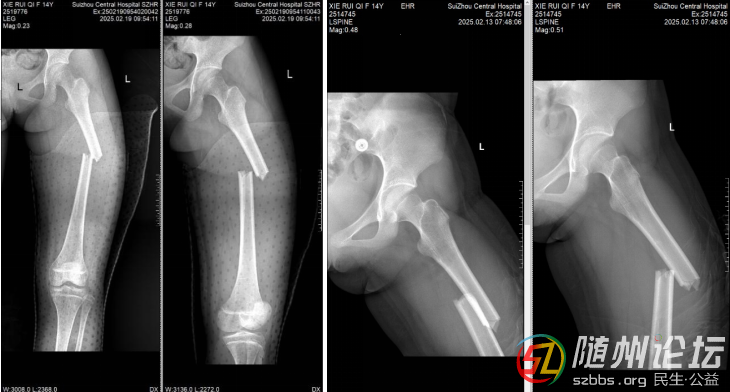

近日,隨州市中心醫(yī)院創(chuàng)傷骨科成功完成首例青少年股骨骨折髓內(nèi)釘固定術(shù)。該手術(shù)運(yùn)用全閉合微創(chuàng)技術(shù),為一名青少年患者實(shí)施了股骨干骨折治療,術(shù)后患者恢復(fù)良好。此次手術(shù)的成功,不僅填補(bǔ)了隨州地區(qū)在青少年股骨骨折 ...